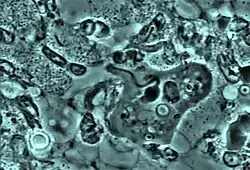

L'exonucléophagie consiste en l'absorption du noyau du polynucléaire neutrophile par l'amibe Entamoeba gingivalis lors des parodontites chroniques et agressives. Ce phénomène laisse en place des globules blancs énucléés hors contrôle dans le biofilm de la gencive infectée et serait à l'origine de destruction tissulaire.